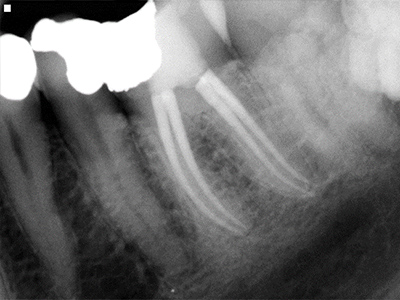

Treatment usually involves an injection to numb the tooth and then the removal of the nerve, washing (disinfecting) out the canal space where the nerve was and then subsequently filling up the root space.